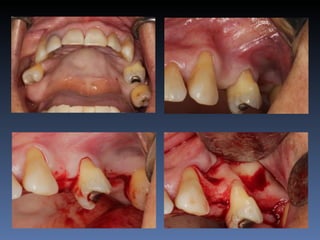

Dominga Maria silva

Idade – 53 anos

Sexo – Feminino

Raça – Caucasiana

ASA – II

Data- 23-04-2012

Diagnóstico:Desdentada parcial maxila

Plano de tratamento:      Reabilitação com 6 blocos

“onlay” provenientes de Úmero fresco-congelado

(FFB); reabertura para instalação de 6 implantes

dentários endo-ósseos e reabilitação protética fixa.